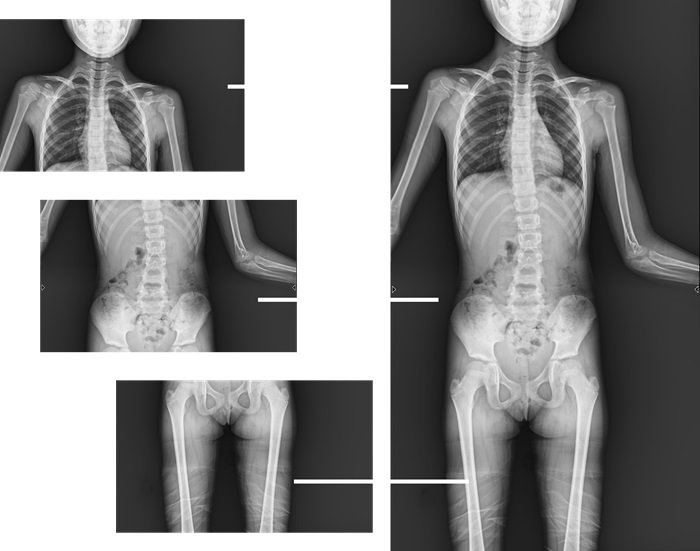

而且,影像采集幅面大,17×17英寸超大視野可覆蓋成年人的全胸全腹,并且能在連續(xù)動(dòng)態(tài)中實(shí)時(shí)高清點(diǎn)片,從而達(dá)到精準(zhǔn)診斷的目的。設(shè)備靈活高效的多維度運(yùn)動(dòng)設(shè)計(jì),也帶來(lái)了更加智能化、人性化操作體驗(yàn),可大幅提升檢查效率。

與此同時(shí),普利德動(dòng)態(tài)平板DRF還具有全身拼接功能,尤其適用于全脊柱和全下肢攝影,為臨床提供高精度圖像,輔助脊柱畸形矯形治療、康復(fù)檢查。